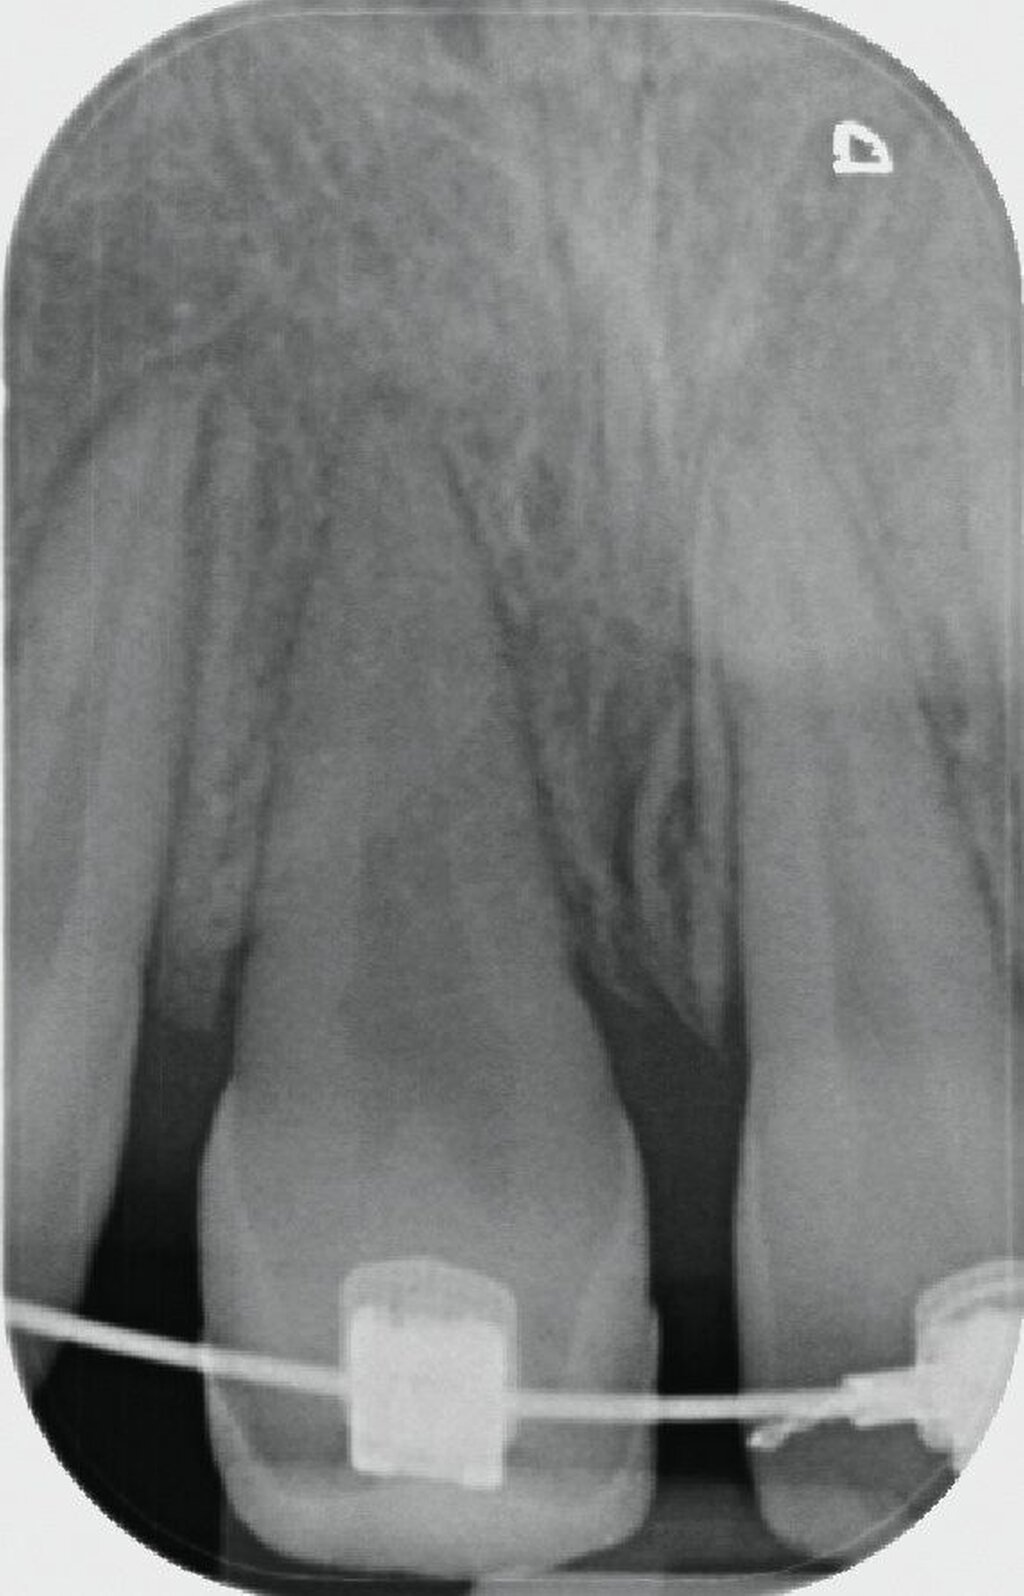

Im Alter von 13,2 Jahren – 4,2 Jahre nach der Milchzahn-TX – stellte sich die Patientin erneut in unserer Praxisklinik vor, um über die weiteren Therapiealternativen zu entscheiden. In enger Absprache mit der behandelnden Kieferorthopädin und den Eltern wurde die Prämolaren-Transplantation als weitere Therapie festgelegt. Auf Wunsch der Kieferorthopädin wurde aus gnathologischen Gründen der Zahn 25 als Transplantat gewählt.

Um störende okklusale Kontakte zu vermeiden, wurde der Zahn in eine leichte Infraposition gestellt und der Biss in der initialen Einheilphase von ein bis zwei Wochen leicht gesperrt, so dass die anschließende kieferorthopädische Extrusion des Zahnes ungestört durchgeführt werden konnte. Mit der kieferorthopädischen Bewegung und Feineinstellung des Transplantats wurde ab der vierten postoperativen Woche begonnen.

Durch die 90-Grad-Rotation des Transplantats stellt sich der Zahn anatomisch in der okklusalen Ansicht (Abbildung 7a) in der Sagittalen nahezu so breit dar wie der Nachbarzahn 21. Der adhäsive Frontzahnaufbau erfolgte drei Monate postoperativ noch unter der kieferorthopädischen Bracketierung. Die Weichgewebshöhe am Transplantat 11 ist durch die kieferorthopädische Extrusion ebenfalls als isogingival zum Nachbarzahn 21 zu erkennen. Der Klopfschall am TX-Zahn 11 war normoton und wies keine Ankylose auf. Die Sensibilitätsprüfung des Zahnes war positiv. Die Obliteration der Zahnwurzel weist auf eine vitale Reaktion des Pulpagewebes hin, wie man sie auch bei erfolgreich replantierten jugendlichen Zähnen beobachtet.

Nach dem Erreichen der isogingivalen Höhe des Zahnfleischrandes durch die kieferorthopädische Extrusionstherapie konnte die Zahnkrone des Transplantats zeitnah ästhetisch aufgebaut werden (Abbildung 7c). Die Entscheidung, auf welche Art die Lücke an der Entnahmestelle des Transplantats geschlossen wird, obliegt den Kollegen der Kieferorthopädie. Die Überlebens- und Erfolgsraten der Prämolaren-Transplantation sind heutzutage so gut, dass die Methode in jedem Fall den Patienten empfohlen werden kann. In einer aktuellen Studie berichten Louropoulou et al. an 910 in die Oberkieferfront transplantierten Prämolaren, dass die 10-Jahres-Überlebens- und -Erfolgsraten beim jugendlichen Patienten 99,8 Prozent betragen [Louropoulou et al., 2023]. Insofern sollte diese chirurgische Methode im Fall eines nicht erhaltungswürdigen Frontzahns im Jugendalter unbedingt mit in die differenzialtherapeutischen Überlegungen einbezogen werden [Andreasen et al., 2009; Louropoulou et al., 2023].